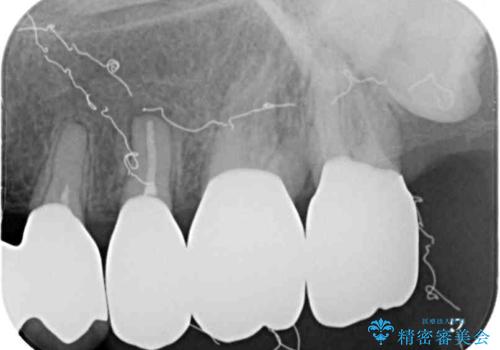

歯周ポケット検査を行ったところ、6-8mmの歯周ポケットが散見され(正常では3mm以下)、歯周病治療が必要と判断されました。

仮歯に置き替え、歯周外科処置(APF、歯肉弁根尖側移動術)による歯周ポケット除去を行った後に、オールセラミッククラウンにて補綴することとしました。

歯周外科処置により歯周ポケットを除去することができ、クラウン装着後はブラッシング時の出血や歯肉の腫れが気にならなくなりました。